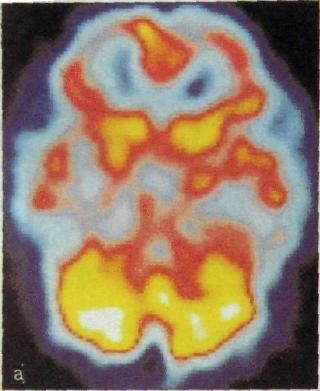

Для изучения формы  ЩЖ а также определения степени накопления РФП применяется сцинтиграфия. Равномерное накопления РФП представлено на рис. 31.

Рис. 31. Сцинтиграмма нормальной щитовидной железы.